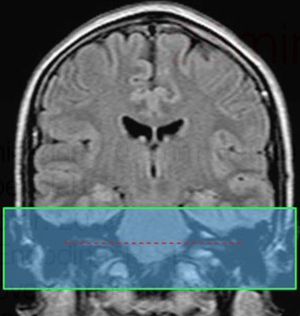

Slice prescription boundaries and orientation for axial imaging of the IAC

Angle the position block parallel to the line along right and left IAC (internal acoustic canal).